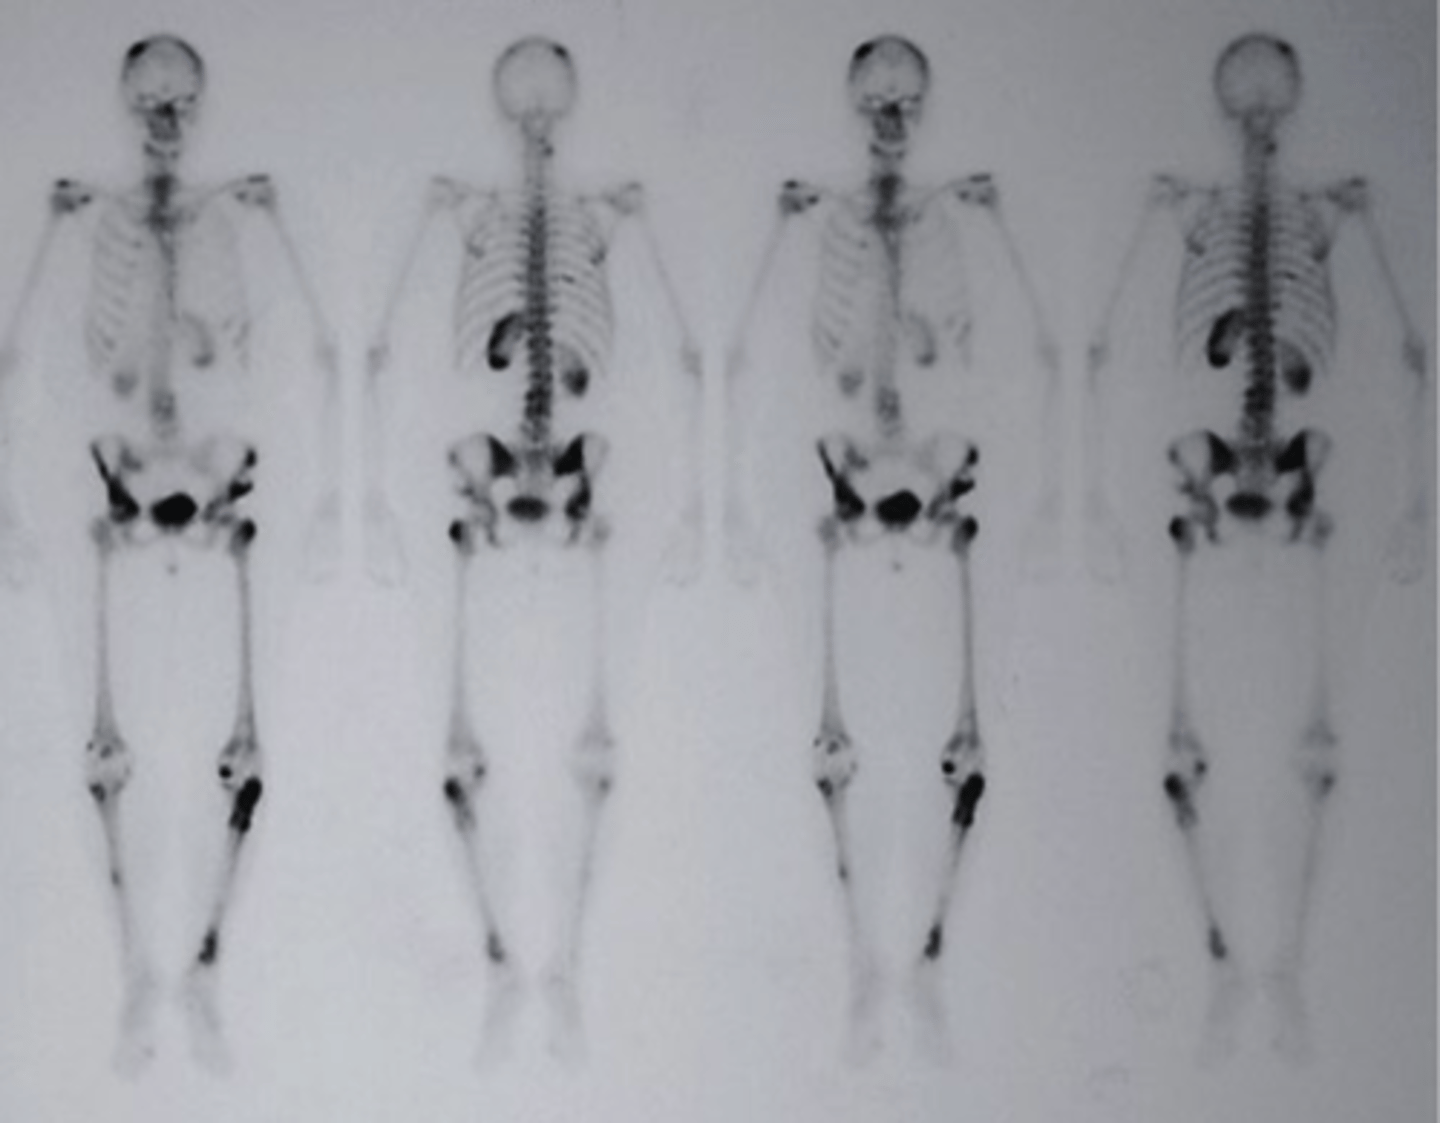

Radionuclide bone scan

what type of imaging study is this?

a. Radionuclide bone scan

b. ultrasound

c. PET scan

d. mammogram

multiple skeletal metastases

which of the following would be the correctly associated image findings?

a. bone fracture

b. epiphyseal plates

c. multiple skeletal metastases

d. Blood Clots